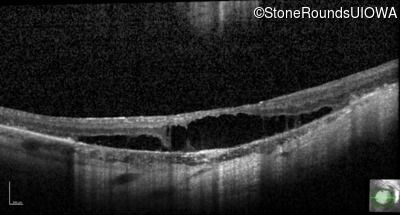

Optical Coherence Tomography - Left - 20/100 -1

Exemplar / OCT Stack